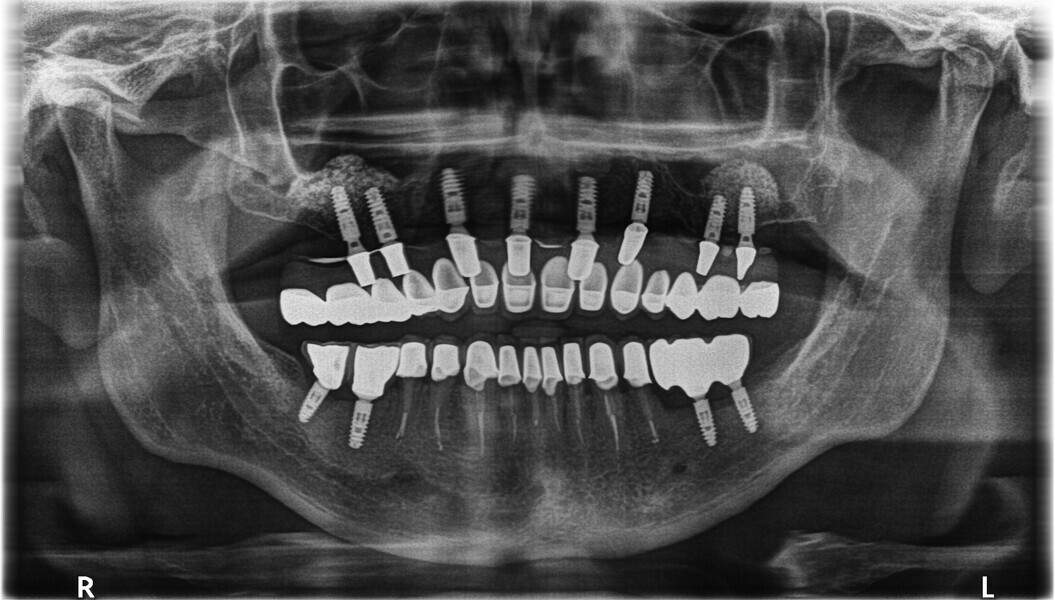

Fig. 30: OPG after placing implants.

Fig. 31: OPG after exposing implants at the lateral section and having used a temporary prosthesis based on telescopes.

Fig. 32: OPG after treatment.